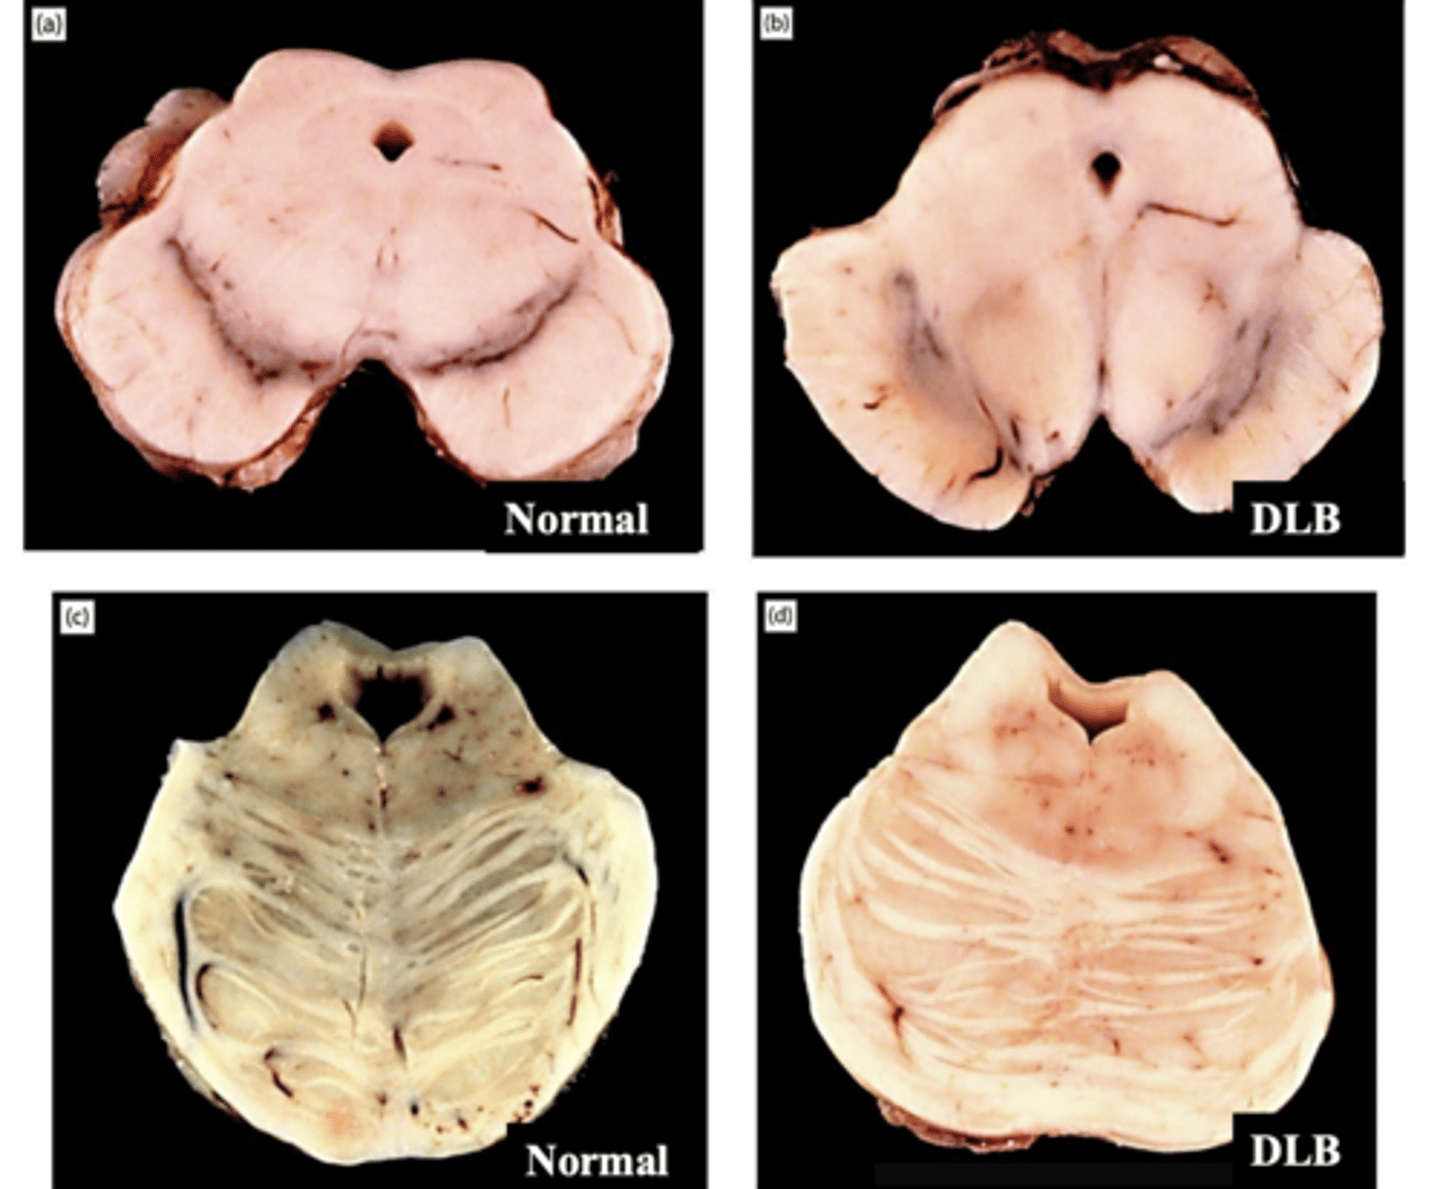

hypopigmentation of substantia nigra (top) and hypopigmentation of locus coeruleus (bottom)

KNOW THIS